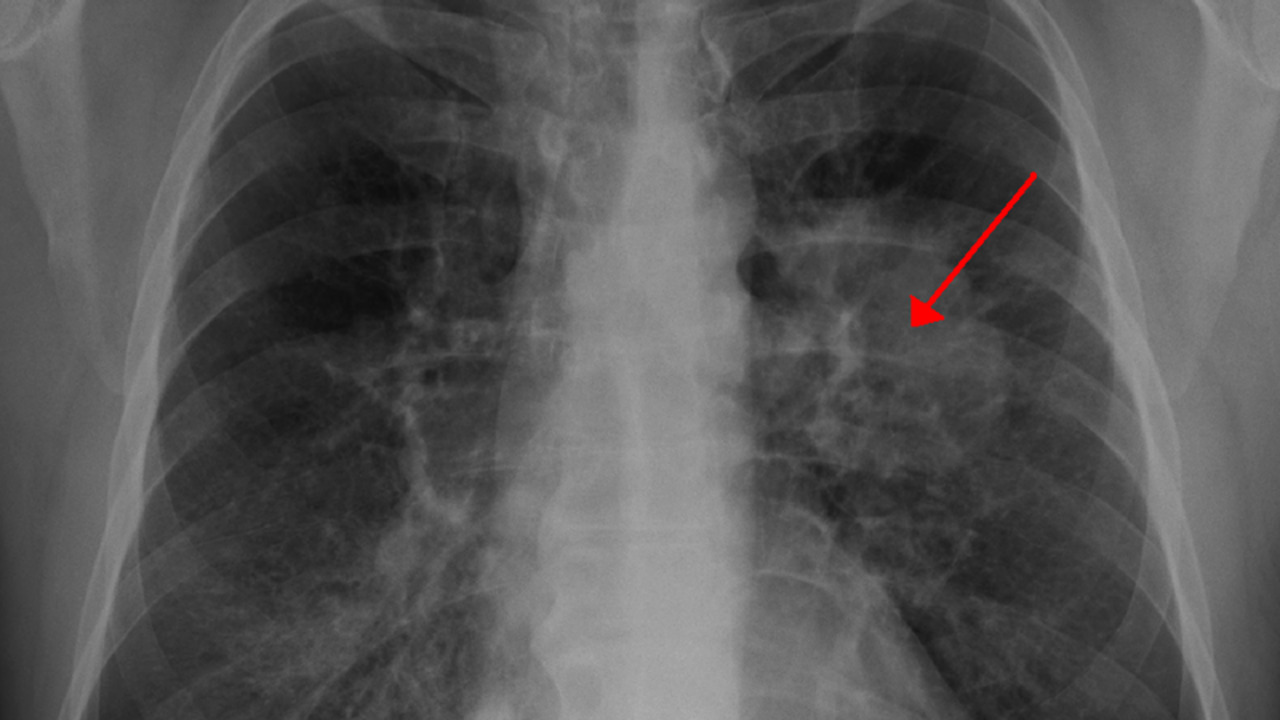

الأشعة التصويرية: وهي كثيرة ومنتشرة في جميع الدول، فيمكن أن نقوم بعمل تصوير رنين مغناطيسي من أجل التعرف على المرض، أو أيضًا التصوير الطبقي، كما أن هناك نوع آخر من أنواع التصوير يُمكن أن نكتشف منها مرض سرطان الرئة وهي المقطعي المحوسب.